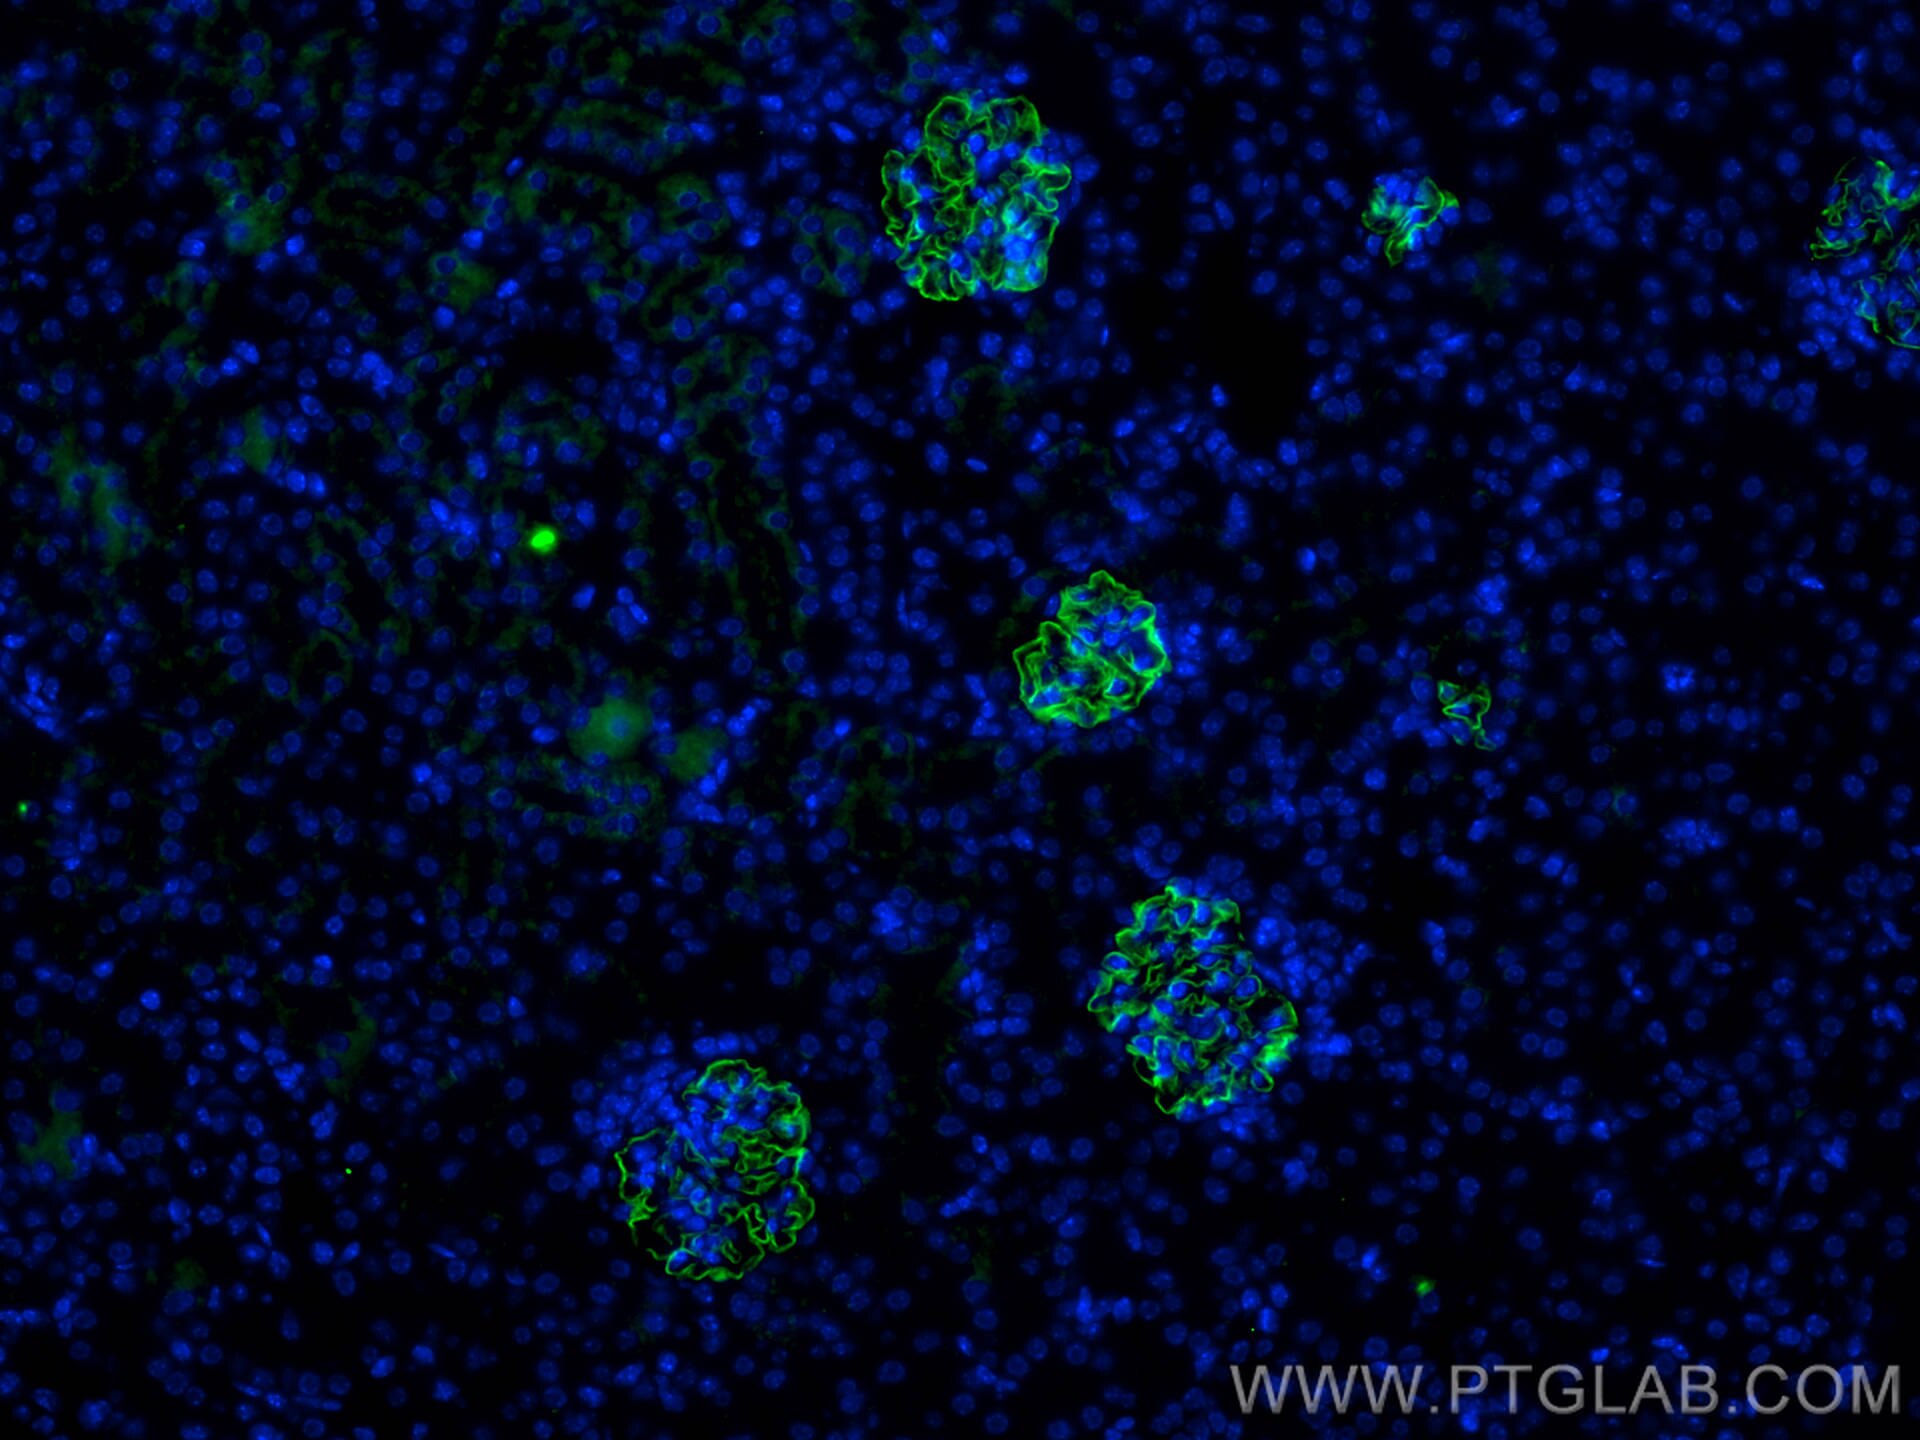

| Positive IF detected in | mouse kidney tissue, zebrafish embryos |

| Immunofluorescence (IF) | IF : 1:300-1:1200 |

NPHS2 (also known as Podocin) is a membrane protein located on the podocyte foot process and is the critical component of the glomerular filtration barrier. Mutations of NPHS2 cause recessive steroidresistant nephrotic syndrome. Two isoforms of NPHS2 exist with molecular weights of 42 kDa and 35 kDa, respectively. (PMID: 21499232)